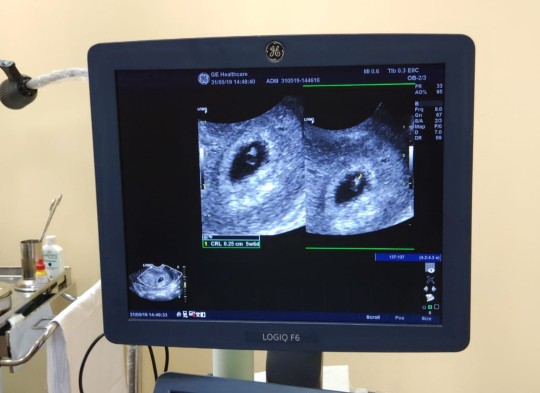

Memang kyk gtu bun, aku 7w udh klytan dedenya lewat USG Transv

Saya 5w6d udah ada bun pas pake transvaginal, kalau diUSG kosong